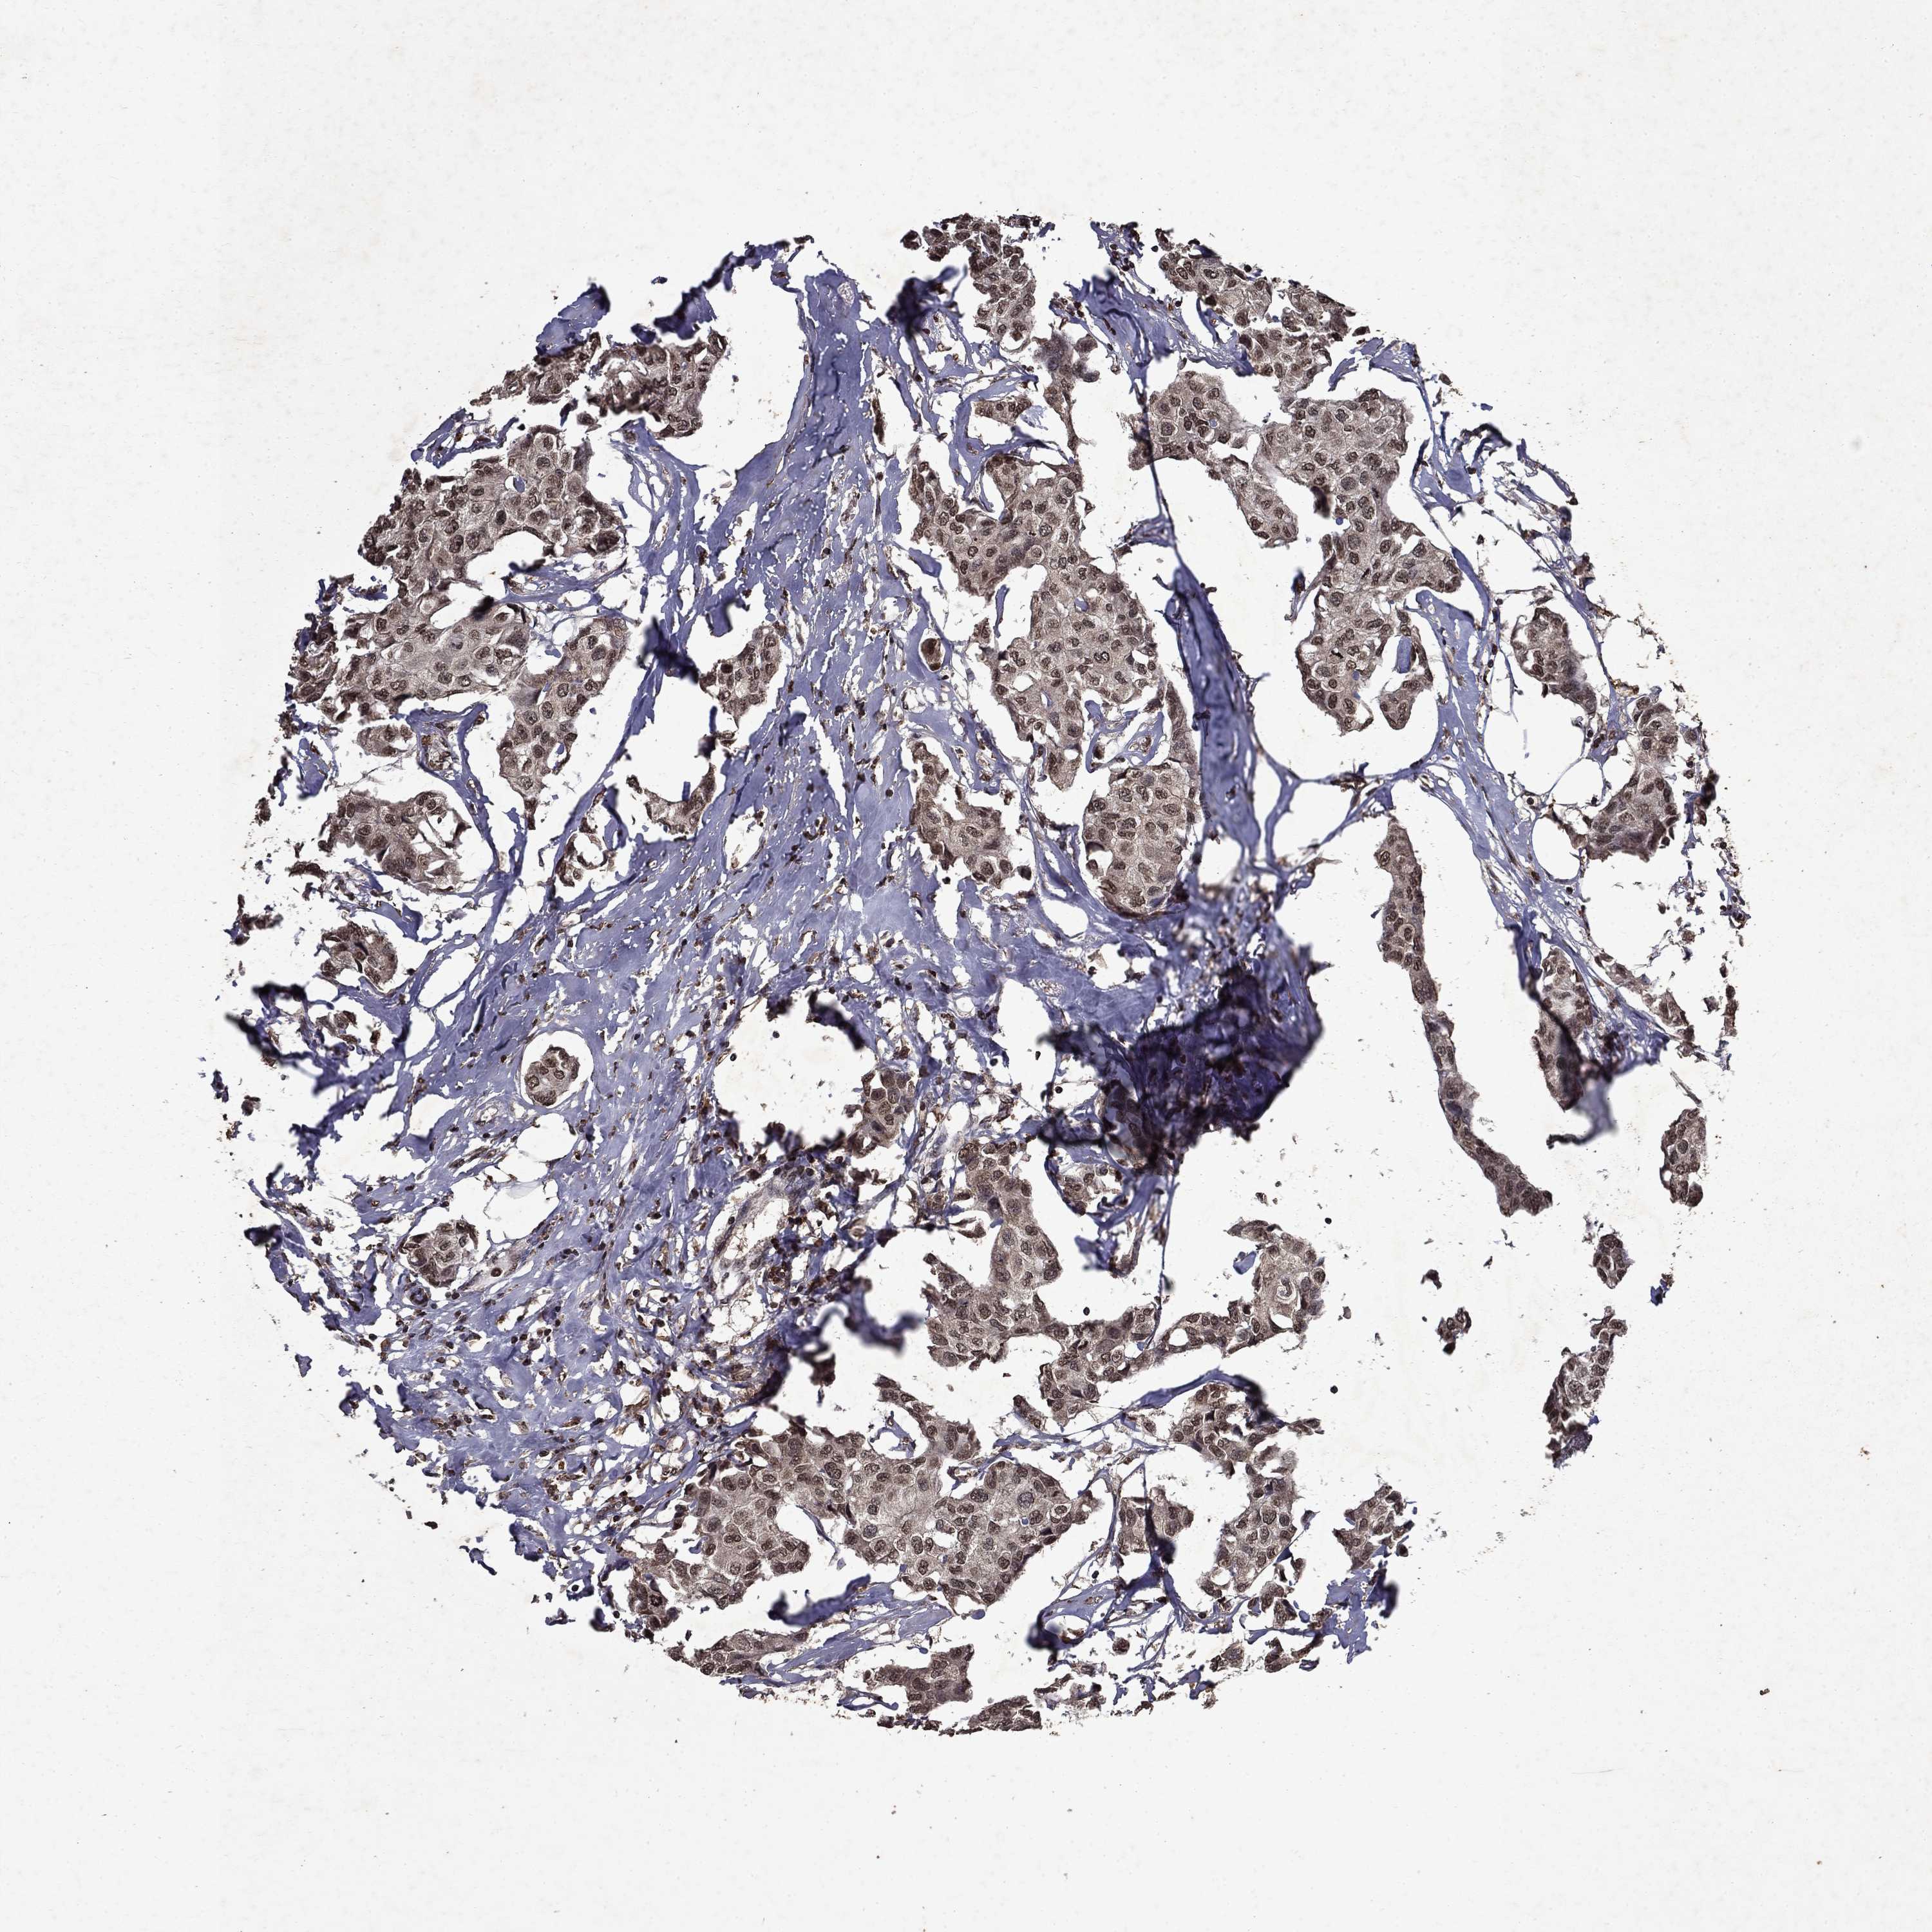

Breast cancer

Human cancer